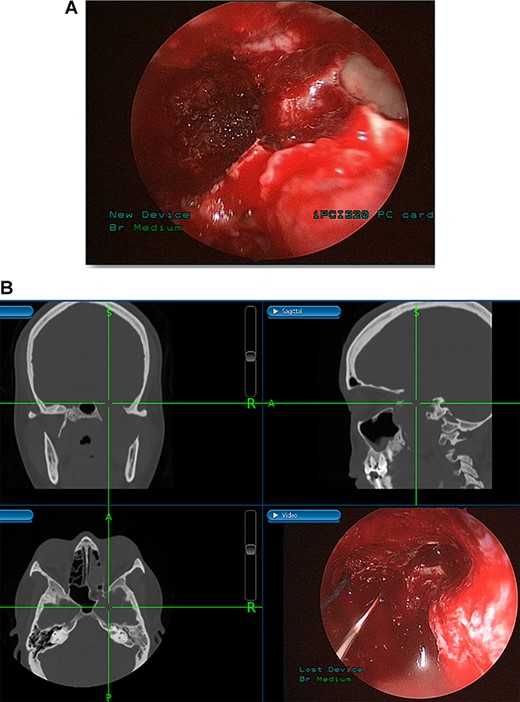

(A) Endoscopic view of the final surgical cavity after tumor removal. (B) Image-guided tumor removal from cavernous carotid artery.

The patient underwent an image-guided endonasal endoscopic tumor removal starting by endoscopic medial and posterior walls maxillectomies to control the tumor removal from the lateral sphenoid sinus and the infratemporal fossa after cauterization of the maxillary artery and sphenopalatine artery branches feeding the tumor. The tumor was dissected and removed from the cavernous (Fig. 3A) and petrous carotid artery in the middle cranial fossa (Fig. 3B). The middle cranial fossa’s dura was intact during the tumor removal (Fig. 3C). All the steps of tumor removal were controlled and monitored under image-guided navigation for accurate localization of tumor removal and avoidance of violation to the middle cranial fossa’s dura, or the brain, and the internal carotid artery in its cavernous and petrous segments (Fig. 4a and b).

Tumors in the infratemporal fossa require extensive approach such as middle fossa extraduaral approach, infratemporal fossa extradural approach, transmaxillary approach, transmandibular approach or transcervical approach. Complications from these procedures include cosmetic problems, facial nerve dysfunction, hearing loss and dental malocclusion. Image-guided endoscopic surgery allows for the preservation of intracranial structures, internal carotid artery and cranial nerves. Moreover, this procedure aids in rapid localization of the anatomical structures and meticulous intervention restricted to tumor margins. The screen is divided into four sections allowing visualization of the tumor from axial, coronal and sagittal views [10].